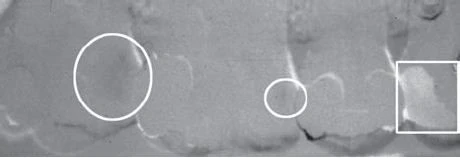

Những sai sót khi phân tích tổn thương ngà răng ở mặt nhai bao gồm việc hình ảnh những hố mặt nhai chồng lên nhau cùng có liên quan hoặc không có liên quan đến tổn thương sâu răng hoặc một miếng trám composite, vốn nhìn giống như tổn thương mặt nhai hoặc một rãnh sâu. Việc khám trực tiếp trên lâm sàng thường loại trừ đi những nhầm lẫn như vậy. Khi tổn thương mặt nhai khu trú ở phần men răng, phần men xung quanh thường che mất tổn thương này. Khi quá trình sâu răng tiến triển, có một đường thấu quang lan rộng dọc theo đường nối men ngà. Khi tổn thương lan rộng vào phần ngà, bờ giữa sâu răng và phần ngà lành mạnh có thể chồng lên nhau và che mất đường thấu quang tại đường nối men ngà. Do đó, đối với những tổn thương còn nông thì tỉ lệ dương tính giả có thể cao ngang với tỉ lệ âm tính giả. Một kết quả âm tính giả có thể không phải là một sai lầm nghiêm trọng do trong hầu hết các trường hợp sâu răng tiến triển chậm và tổn thương được phát hiện ở một thời gian sau đó. Một kết quả dương tính giả có thể dẫn đến việc bề mặt răng lành mạnh bị xâm phạm không thể hồi phục được. Ngoài ra, khi có một sự khác biệt về mật độ rõ rệt, chẳng hạn như giữa men và ngà, thì có thể có một vùng thấu quang ngay gần men răng. Đây là một ảo giác quang học gọi là dải Mach (hình minh hoạ bên dưới). Nó có thể tạo nên nhiều kết quả dương tính giả; vì vậy, nên theo dõi những trường hợp này và từ chối việc điều trị can thiệp.

Tổn thương sâu răng ở mặt ngoài và mặt trong thường xảy ra ở những hố rãnh trên men răng. Khi tổn thương nhỏ, chúng thường có hình tròn; khi lan rộng lên, chúng thường có hình elip hoặc hình bán nguyệt. Chúng có bờ rõ ràng, giới hạn rõ. Có thể khó để phân biệt giữa tổn thương mặt ngoài hay mặt trong trên X quang. Khi quan sát tổn thương mặt ngoài hoặc mặt trong, bác sĩ lâm sàng sẽ tìm thấy một vùng men không sâu răng với mật độ đồng nhất bao xung quanh một vùng thấu quang rõ ràng. Vùng hình tròn có giới hạn rõ này biểu hiện phần men răng không sâu răng song song bao xung quanh tổn thương mặt ngoài và mặt trong. Tuy nhiên, tổn thương mặt nhai thường lan rộng hơn sâu răng mặt ngoài hoặc mặt trong, và đường viền của cúng không có giới hạn rõ. Đánh giá trên lâm sàng bằng cách quan sát và thăm khám để chẩn đoán xác định tổn thương mặt ngoài hoặc mặt trong.